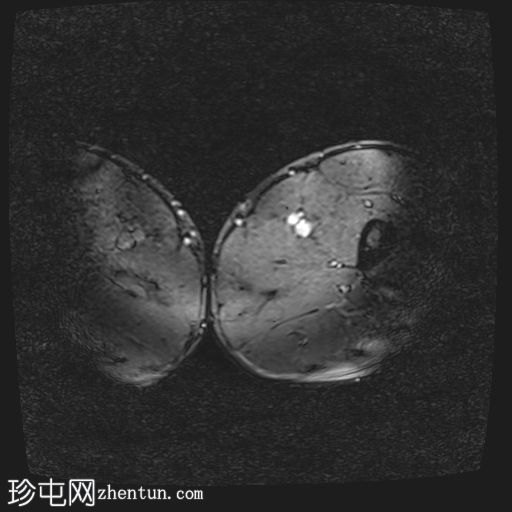

轴位

T1加权像

股二头肌长头近端和中段可见高信号水肿,大小约10×3厘米。

此外,邻近的半腱肌可见羽毛状水肿,大小约5×2厘米。

未见肌内积液或血肿。

邻近肌间隙可见一条粗液线,延伸至近端和远端肌腱连接处。

股二头肌腱近端和中段轻度增厚,呈波浪状轮廓,腱周积液延伸至肌腱连接处。然而,未发现撕裂。